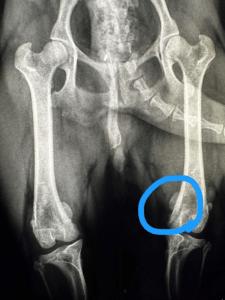

犬の場合、破折が最も多いのは「上顎の犬歯(大きなキバ)」と「上顎第4前臼歯(奥歯の中で最も大きい歯)」(症例写真📸)です。

・レントゲンでの歯根や歯髄の状態

特にレントゲン検査は、見た目ではわからない内部の感染を発見する上で欠かせません。